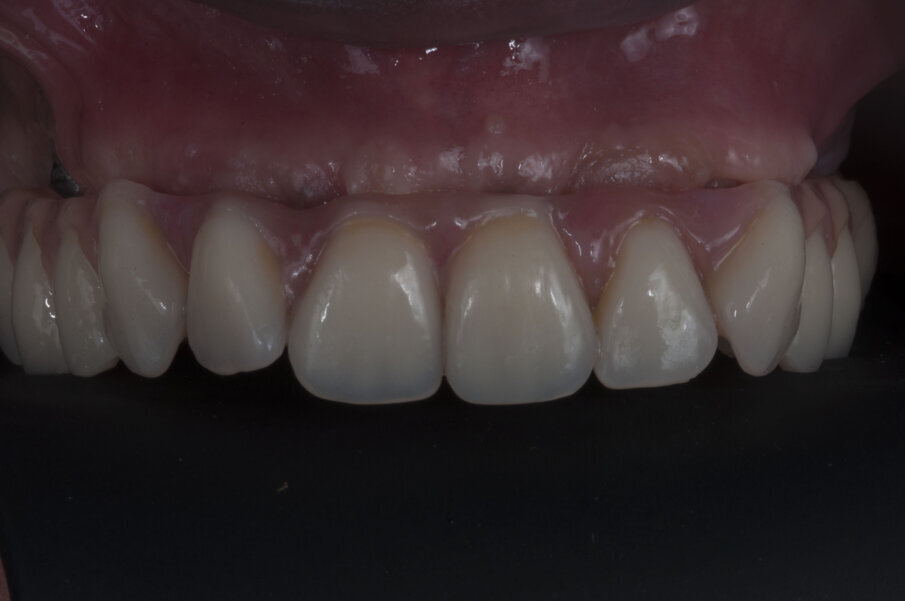

Nel frattempo il laboratorio, avendo l’impronta fin dal giorno della chirurgia, ha provveduto a fabbricare il modello maestro sul quale preparare un primo provvisorio avvitato da inserire sessanta giorni dopo la chirurgia (Figg. 29-32). La struttura definitiva viene disegnata e prodotta con tecnologia CAD/CAM da Dentsply Sirona con il programma Atlantis (Figg. 33, 34). Una volta prodotta la struttura viene provata in bocca (Figg. 35, 36) e, dopo averne testato la precisione e l’adattamento, il laboratorio procede al confezionamento della protesi definitiva (Fig. 37).

Verificata la precisione del lavoro si procede alla consegna. La Fig. 38 evidenzia la perfetta salute dei tessuti peri-implantari a protezione dei MUA, e nelle figure 39 e 40 evidenziano l’ottimo adattamento del manufatto finale ai tessuti intra ed extra-orali. La panoramica di controllo a 12 mesi dal completamento del lavoro evidenzia una perfetta stabilità dei livelli ossei dopo il carico protesico (Fig. 41).